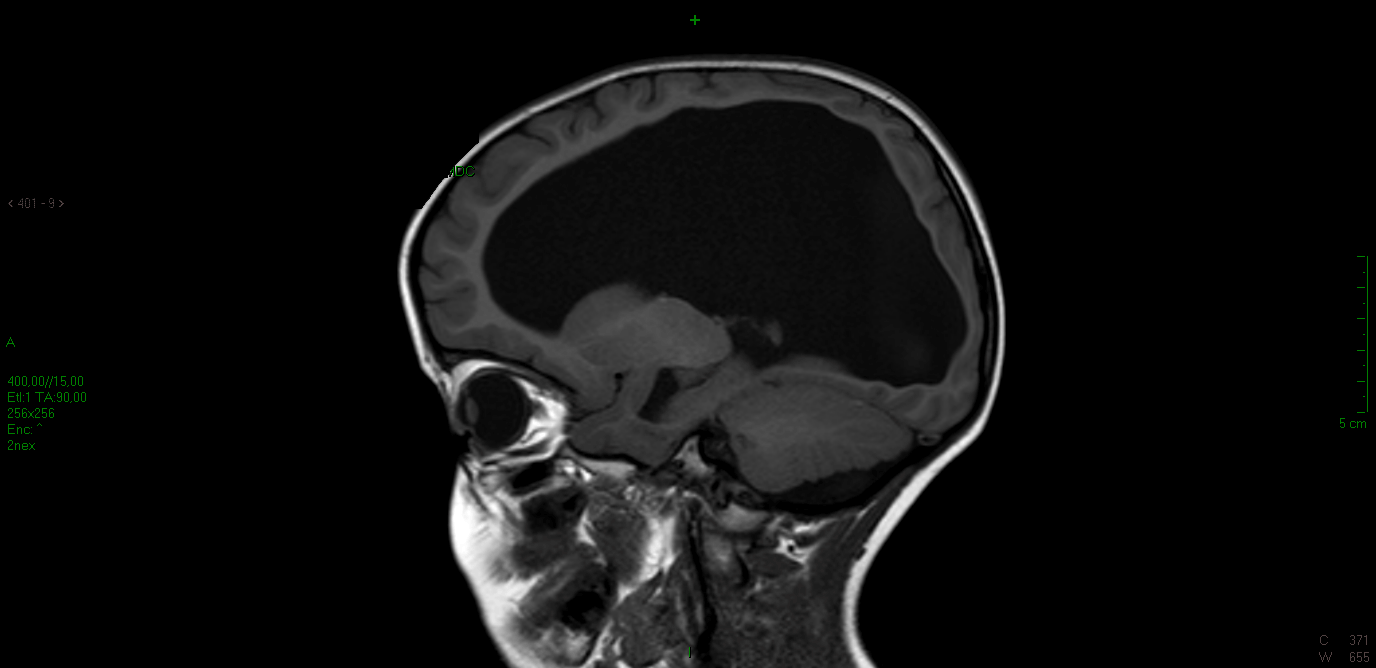

Eseguiamo finalmente la tanto attesa RMN che mostra: �idrocefalo tetraventricolare di grado severo e cisti liquorale retro e sottovermiana compatibile con tasca di Blake persistente. Non segni di ipertensione endocranica� (Figura 1 e Figura 2). Dopo aver escluso cause infettive (in particolare la ricerca di CMV DNA � negativa) e aver eseguito l�esame del fundus oculi che rileva papille pallide a limiti netti (con potenziali evocati visivi nella norma), confermiamo la diagnosi malformativa.

Figura 1. Idrocefalo tetraventricolare in sezione sagittale(RMN pre-intervento)